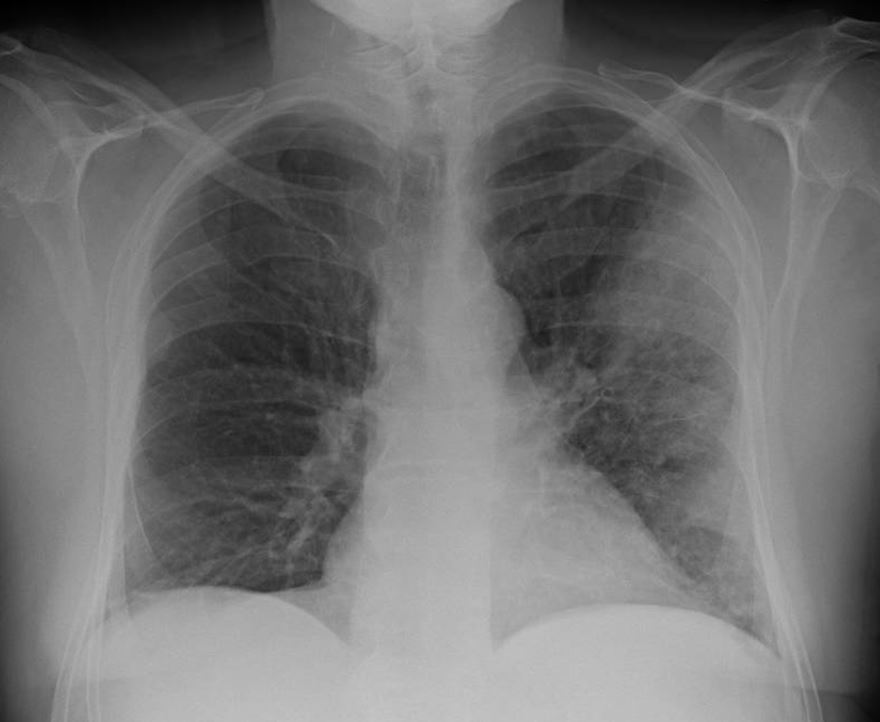

legionella case 2